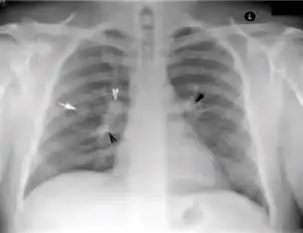

3. Nodule with poorly defined margins - Round density within the lung parenchyma, also called a tuberculoma. Nodules included in this category are those with margins that are indistinct or poorly defined (tree-in-bud sign[3]). The surrounding haziness can be either subtle or readily apparent and suggests coexisting airspace consolidation.

7. Other - Any other finding suggestive of active TB, such as miliary TB. Miliary findings are nodules of millet size (1 to 2 millimeters) distributed throughout the parenchyma.